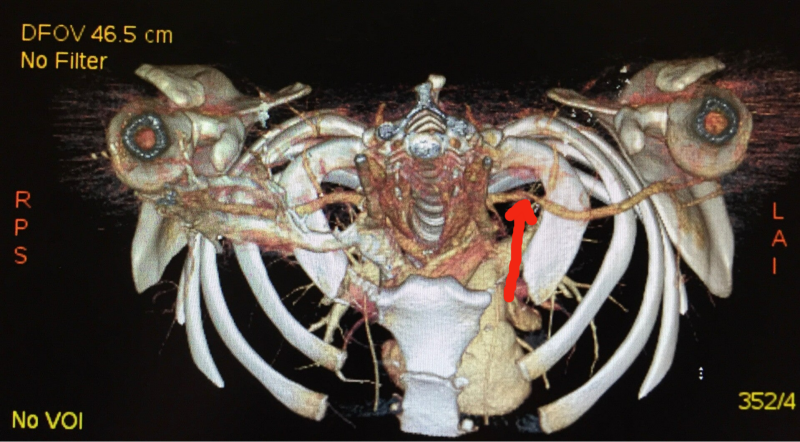

In der Angio-CT Untersuchung in Provokationsstellung, also mit erhobenen Armen, lassen sich nicht nur die Gefässstrukturen sondern insbesondere auch die knöchernen Gegebenheiten rekonstruieren und somit auch subtilere positionsbedingte Irritationen anschaulich in Relation dazu darstellen. In den beiden Beispielbildern lässt sich die Gefässbeteiligung nur durch besondere Blickwinkel ausreichend visualisieren.